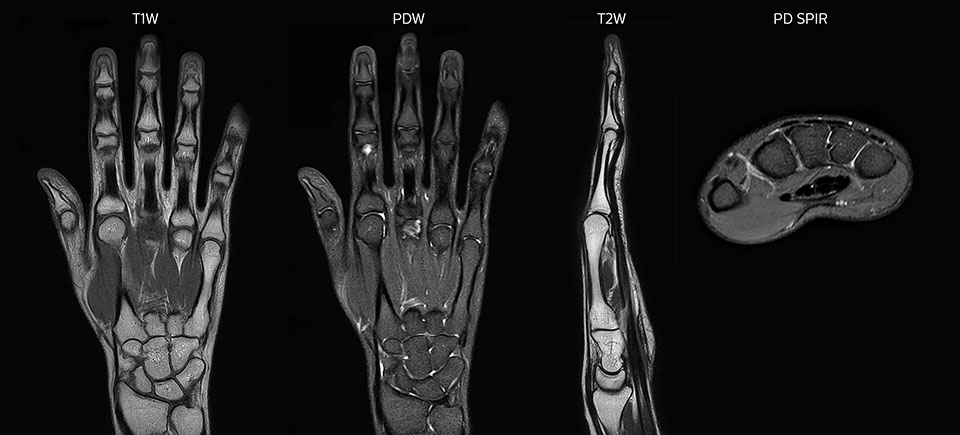

Prodiva imaging of the hand covers the fingertips and includes the full wrist as well. The dS MSK M coil is easy to use.

Scan time 2:55 min, FOV 160 mm, acq voxels 0.55 x 0.83 x 3.0 mm.

Scan time 4:19 min, FOV 160 mm, acq voxels 0.55 x 0.80 x 3.0 mm.

Scan time 2:50 min, FOV 160 mm, acq voxels 0.70 x 0.99 x 3.0 mm.